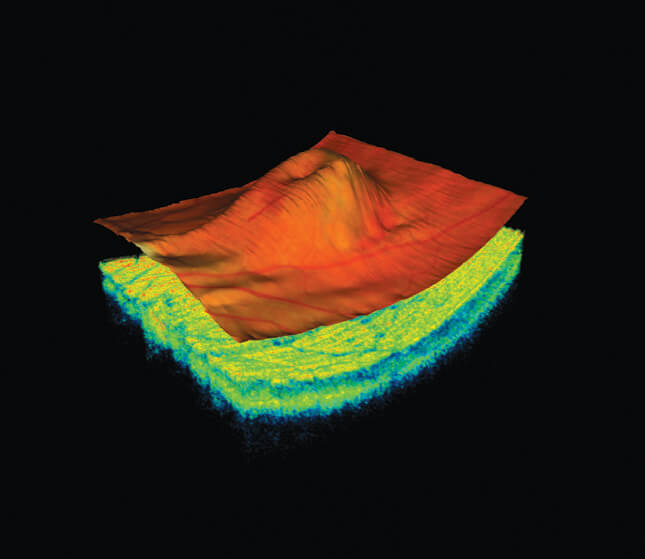

Optical Coherence Tomography (OCT) is an advanced eye scan, similar to ultrasound. The OCT uses light rather than sound waves to illustrate the different layers that make up the back of the eye. Within 2 seconds, the OCT takes over 30,000 individual scans of the back of the eye and this is used to produce a 3D image of the retina and optic nerve. The scan gives an accurate cross-sectional map through the retina and allows examination of the back of the eye in incredibly fine detail.

You will also get to see an instant 3D high definition image of your eyes.